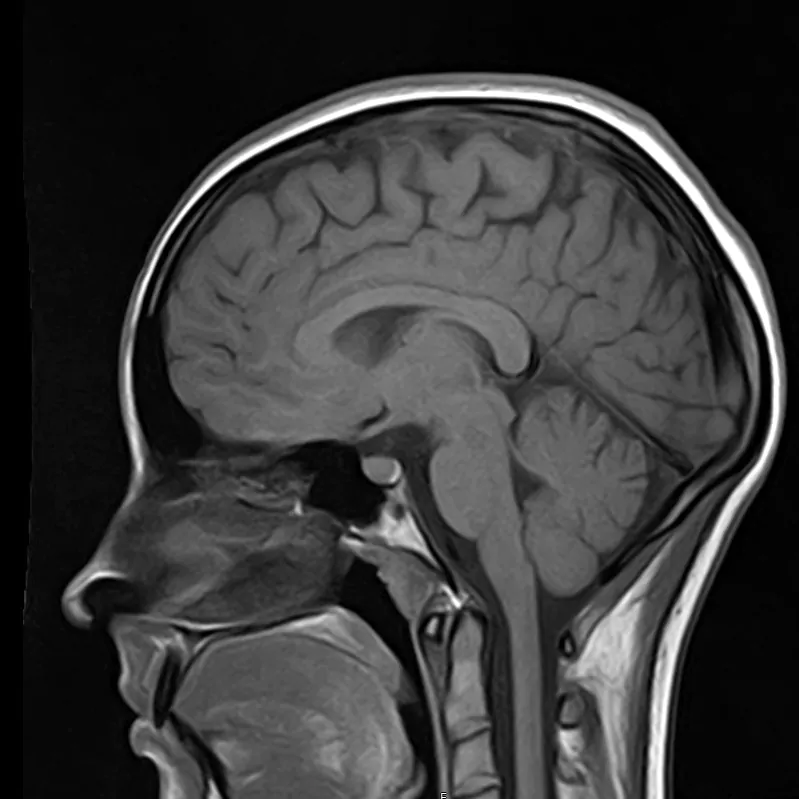

3️⃣ При головной боли, надо обязательно сделать МРТ

Действительно, зачастую приходят на МРТ пациенты, страдающие головной болью. Однако, в подавляющих случаях, МРТ не дает каких-то неблагоприятных результатов. Такая головная боль, как правило, связана с психоэмоциональными или психофизиологическими особенностями как организма, так и образа жизни (стресс, переутомление, несоблюдение режима труда и отдыха и т.д.). Но стоит отметить, что проведение МРТ даст дополнительную информацию Вам о состояние головного мозга  и тем самым “успокоит” Вас.